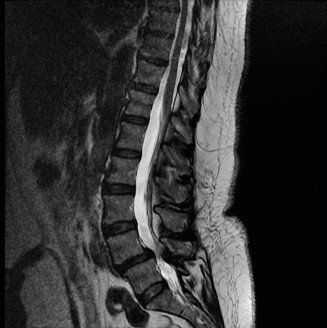

Prognosis of central cord syndrome? Indications for surgery for this disorder? CASE 2 A 56-year-old man presents to you with a chief complaint of severe right buttock, posterior thigh, and lower leg pain for 12 weeks. It radiates to the lateral aspect of his foot, and it is worse with sitting or standing for prolonged periods and with walking. Now over the past 2 weeks, he reports difficulty with toe push-off on the right side. Treatment so far has been nonsteroidal anti-inflammatory drugs (NSAID), physical therapy, and an epidural injection without significant relief. Physical examination findings include 4/5 right ankle plantar flexion, a positive straight leg raise on the right, and an absent right Achilles tendon reflex. Images of his lumbar spine are shown in Figures 1–4 and 1–5.

Figure 1–4

The correct answer is (C). The patient presents with classic right S1 radiculopathy and new onset plantar flexion weakness. The images demonstrate a right-sided paracentral disc herniation at L5/S1 compressing the traversing S1 nerve root. Despite nonoperative management, he continues to have severe pain and new weakness. Continued physical therapy or an epidural injection is unlikely to improve the patient’s pain at this time. In the setting of neurological decline, surgery is more strongly indicated. Lumbar discectomy is the most appropriate procedure for this patient. Fusion would only be indicated if there were radiographic signs of instability, which are not present.